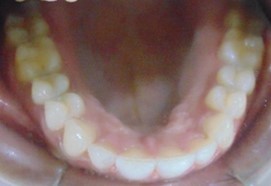

Before

After

Image 1

Image 2

Image 3

Abhinav Jain, 24Y, Duration - 8Months